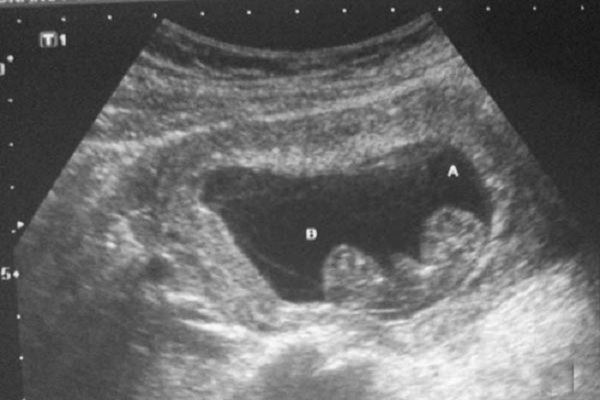

Đảm bảo không có thai xuất hiện ngoài tử cung

Xem được tình hình phôi thai có bám chặt tử cung hay không. Từ đó biết rõ mẹ sẽ không bị có thai ngoài tử cung.